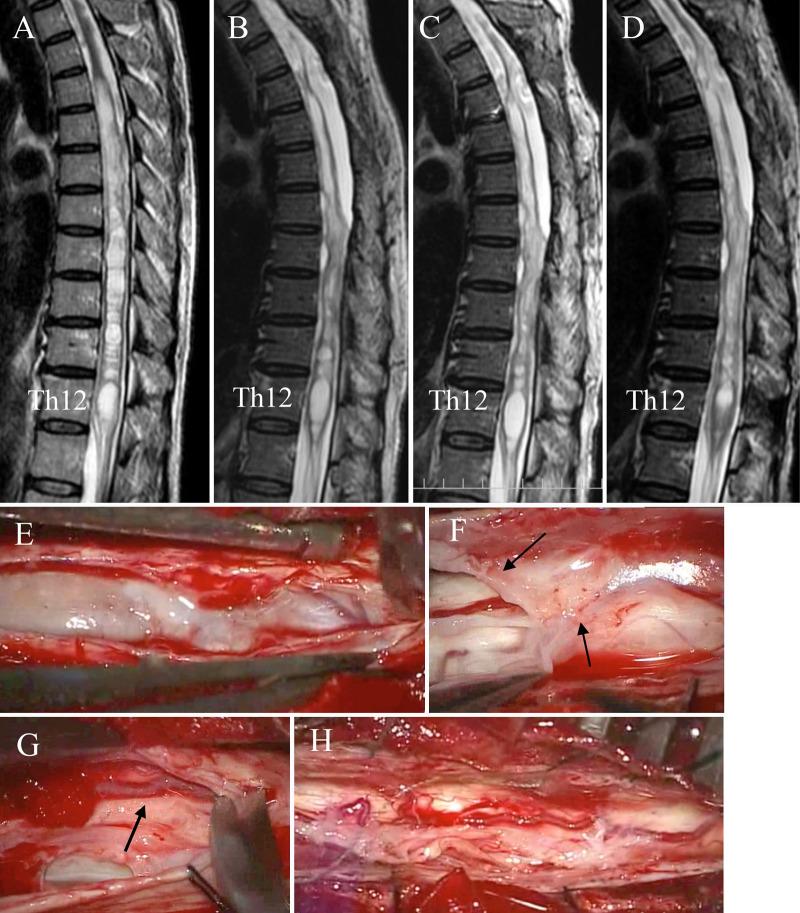

Spinal adhesive arachnoid pathology is a rare cause of myelopathy. Because of rarity and variability, mechanisms of myelopathy are unknown. The authors retrospectively analyzed patients to understand pathophysiology and provide implications for surgical treatment.

OBSERVATIONS

Nineteen consecutive patients were studied. Thirteen patients had a secondary pathology due to etiological disorders such as spinal surgery or hemorrhagic events. They received arachnoid lysis (4 patients), syringo-subarachnoid (S-S) shunt (8 patients) with or without lysis, or anterior decompression. Three of them developed motor deterioration after lysis, and 6 patients needed further 8 surgeries. Another 6 patients had idiopathic pathology showing dorsal arachnoid cyst formation at the thoracic level that was surgically resected. With mean follow-up of 44.3 months, only 4 patients with the secondary pathology showed improved neurological grade, whereas all patients with idiopathic pathology showed improvement.

LESSONS

The idiopathic pathology was the localized dorsal arachnoid adhesion that responded to surgical treatment. The secondary pathology produced disturbed venous circulation of the spinal cord by extensive adhesions. Lysis of the thickened fibrous membrane with preservation of thin arachnoid over the spinal veins may provide safe decompression. S-S shunt was effective if the syrinx extended to the level of normal subarachnoid space.

脊髓粘连性蛛网膜病变是脊髓病的罕见病因。由于其罕见性和变异性,脊髓病的发病机制尚不清楚。作者对患者进行回顾性分析,以了解其病理生理学并为手术治疗提供启示。

观察结果

对19例连续患者进行了研究。13例患者因脊髓手术或出血事件等病因性疾病存在继发性病变。他们接受了蛛网膜松解术(4例患者)、脊髓空洞-蛛网膜下腔(S-S)分流术(8例患者,伴或不伴松解术)或前路减压术。其中3例患者在松解术后出现运动功能恶化,6例患者需要进一步进行8次手术。另外6例患者患有特发性病变,表现为胸段背侧蛛网膜囊肿形成,均接受了手术切除。平均随访44.3个月,只有4例继发性病变患者的神经功能分级有所改善,而所有特发性病变患者均有改善。

经验教训

特发性病变为局限性背侧蛛网膜粘连,对手术治疗有反应。继发性病变通过广泛粘连导致脊髓静脉循环障碍。在保留脊髓静脉上方薄蛛网膜的情况下,松解增厚的纤维膜可提供安全的减压。如果脊髓空洞延伸至正常蛛网膜下腔水平,S-S分流术是有效的。